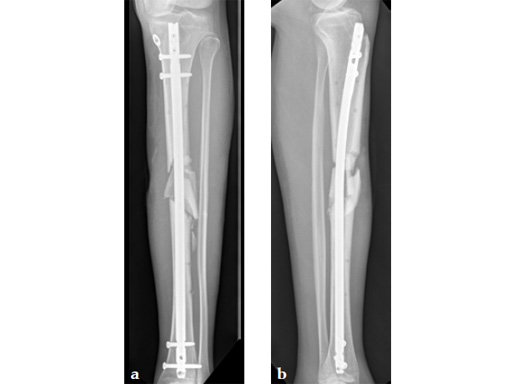

Clinical example of the first patient treated with the new ETN PROtect.

Case 1: A 33-year-old man with a third degree open fracture of his left tibia was initially treated with an external fixator and unilateral compartment release. He had undergone ACL reconstruction in the past.